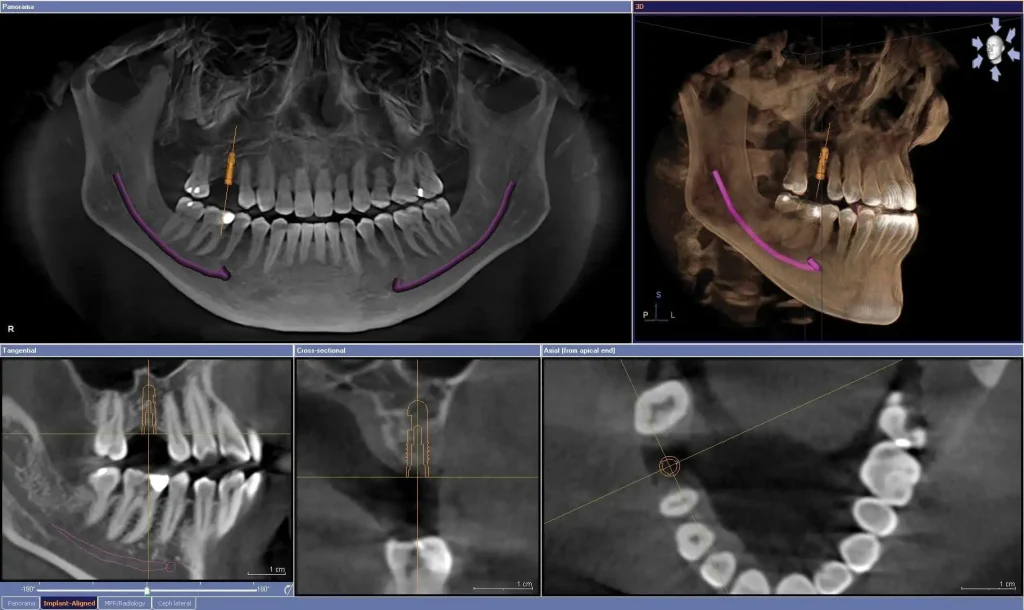

Tomografi, diş hekimleri tarafından sıklıkla kullanılan bir görüntüleme yöntemidir. Tomografi, dişlerin, çenelerin ve çevre dokuların üç boyutlu bir görüntüsünü oluşturmak için kullanılan radyolojik bir tıbbi görüntüleme yöntemidir.

Tomografi genellikle, bir dişin kökünde bir enfeksiyon ya da kist olup olmadığını veya diş implantı yerleştirmeden önce kemik yapısının uygun olup olmadığını belirlemek için kullanılır. Ayrıca, diş çürüğü ve diş eti hastalıkları gibi diş problemlerinin teşhisinde de yardımcı olabilir.